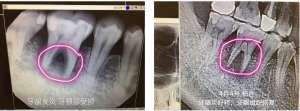

Mára világszerte már több mint 200.000 pozitív tapasztalat mutatja technológiánk rendkívüli hatékonyságát, nem egyszer a csodával határos, már-már szinte meghökkentő tapasztalatokról számolnak be partnereink.

Szeretnénk képzeleted határait tágítani, ehhez kérlek nézd meg oldalunkon a videótárat, illetve keress meg és segítek bejutni titkos Facebook csoportunkba, ahová ezrek töltik fel tapasztalataikat, melyeket szakemberek is értetlenül bámulnak.